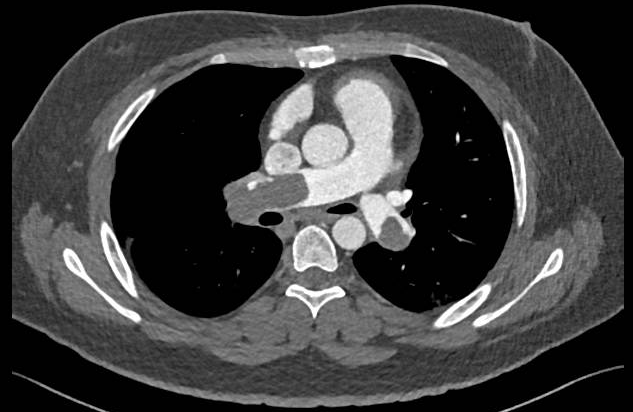

术前肺动脉CTA提示双肺动脉主干栓塞

入院后生命体征:体温36.5℃,脉搏:110次/分,呼吸:23次/分,血压:101/55mmHg(收缩压较平时下降约40mmHg),血氧饱和度90%。心脏超声:右房室大,肺动脉增宽,RV/LV约1.1,肺动脉压约76mmHg。高危证据:血流动力学不稳定、肺栓塞严重指数(sPESI评分):3分、右心室功能障碍。